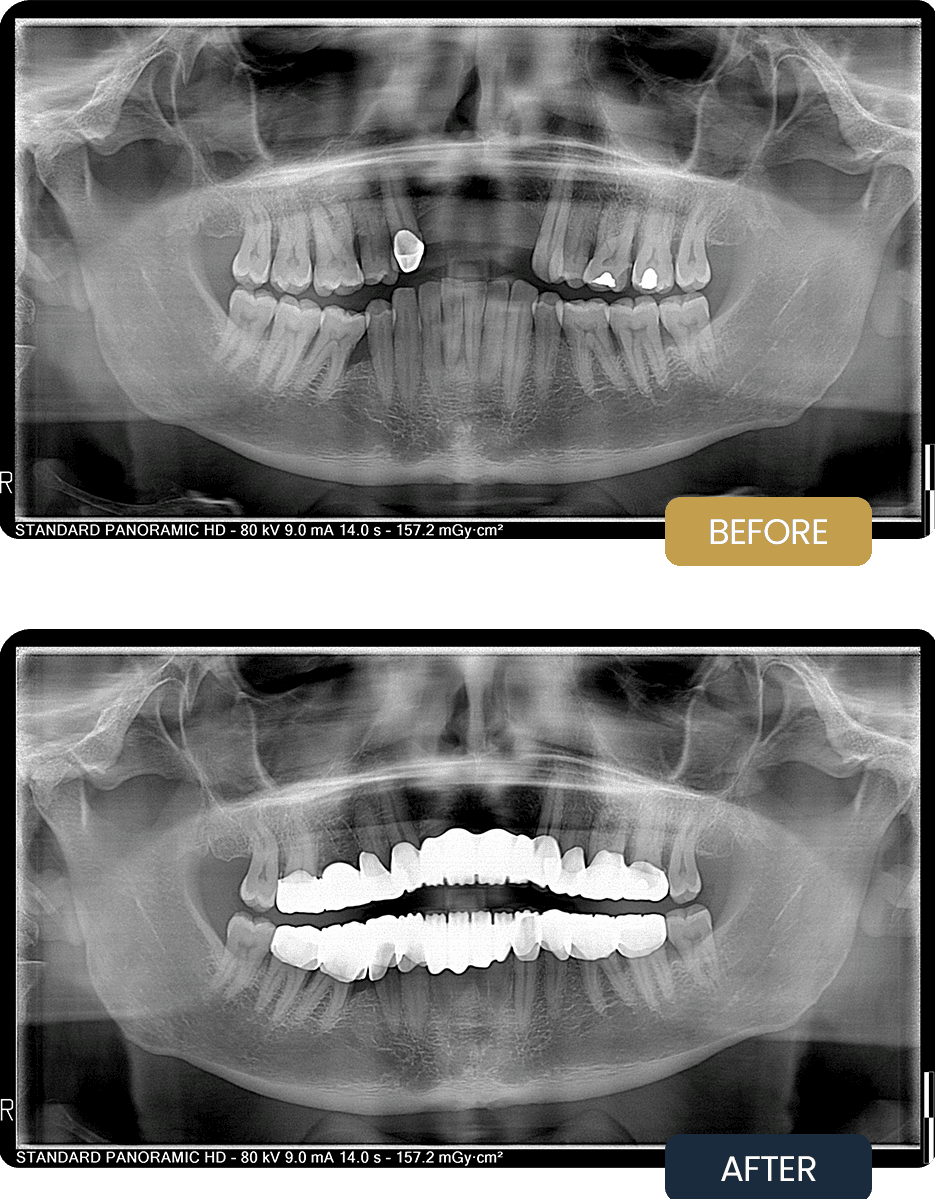

Jason initially presented with multiple compromised teeth, old restorations, and areas of structural damage that could not be preserved.

There was clear evidence of bite imbalance and loss of vertical dimension, leading to uneven chewing forces and increased risk of further dental breakdown. Several teeth required extraction due to poor prognosis, while others needed restorative support to prevent future failure.

Overall, function and aesthetics were significantly compromised prior to treatment.

Post treatment panoramic imaging confirmed successful completion of all planned extractions and accurate placement of 25 crowns across both arches.

The restored dentition demonstrated improved alignment, balanced occlusion, and restored vertical dimension. The upper and lower splints provided additional bite stabilisation and protection, supporting long term durability of the restorations.

Jason’s treatment resulted in a stable, functional bite with improved chewing efficiency, comfort, and overall oral health.